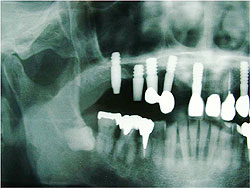

AQBは、結晶体の密度が高く純度も高いことが特長であり、三井記念病院におけるAQBインプラント症例では、最長18年を経過した臨床例においても、歯槽骨の状態は変わらず、逆に密になっていることが分かっている。そこで、上顎臼歯部の骨吸収症例において、サイナスリフトと同時にAQBインプラント1ピースを植立し、自家骨移植や人工骨移植を行わず、治療を行った症例を報告した。6例に施行し、全例、予後良好で、すべて植立後4ヵ月以内で咬合を開始した。GBR症例においてもAQBインプラント2ピースを埋入し、自家骨移植や人工骨移植は行わず、チタン入り非吸収性膜を用いたスペースメーキングを行った。その結果、4ヵ月後には歯槽骨の再生を確認した。

| AQBを用いて歯槽骨再生を図った症例 | |

サイナスリフト症例 ▼ ![]() 術前 ![]() 術直後 ![]() 術後4ヵ月 |